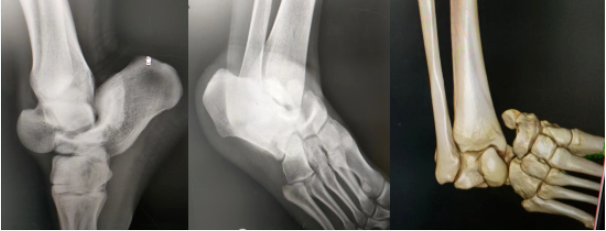

于是马上为小程进行手法复位,一套操作,伴随一声“咔哒”,成功复位!

复位后图片